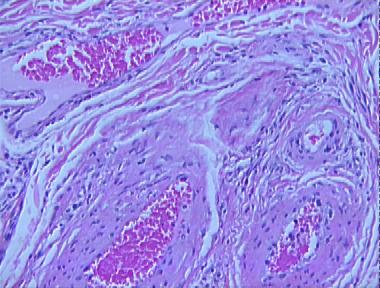

phlebangioma (arterial venous hemangioma)

Histologic Features